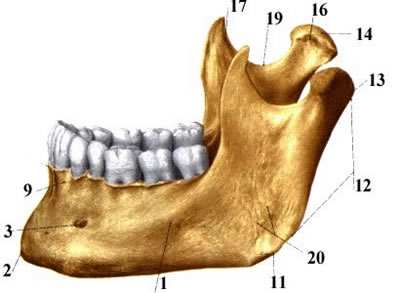

48. Przyczep mięsnia skroniowego

49. więzadło stylomandibulare

50. Angulus mandibulare

51. Incisura mandibulare

52. Tetnica szczękowa tędy przebiega

53. Wychodzą tędny naczynia i nerwy żwaczowe 54. Fovea pterygoidea